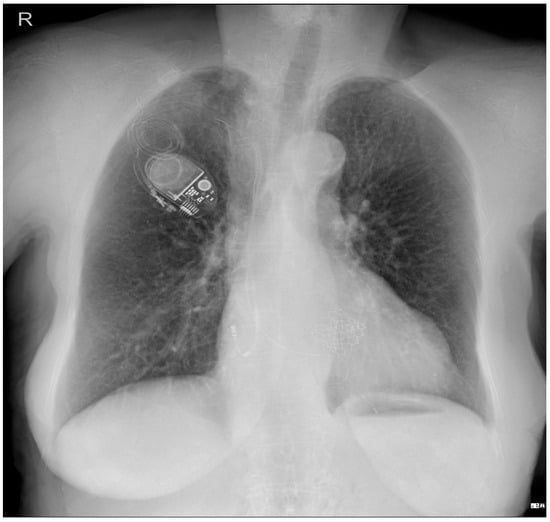

Figure 3.

Echocardiography exam images at admission: A transthoracic echocardiography (TTE) exam was performed in the apical 4-chamber view (a,b) and subcostal view (c,d), revealing the insertion of the pacing probe into the myocardium of the right ventricle free wall, without any visible fractures or ruptures of the lead.